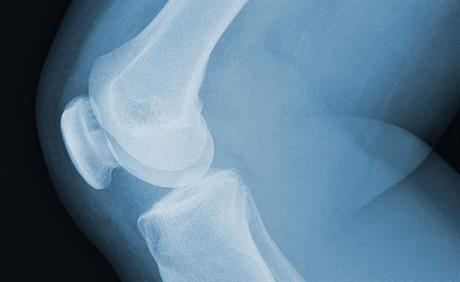

Napuknuće ligamenata koljena

Ukoliko se dobro odradi dio oporavka, tada povratak u sport nije upitan, uz preporuku za kontinuirani rad na održavanju snage mišića

Može li bez operacije koljena?

Ukoliko je oštećenje malo i nalazi se na mjestu koje nije izloženo punom opterećenju kod hodanja, trčanja ili skokova, te ne izaziva simptome kod opisanih aktivnosti, moguće je pristupiti neoperativnom liječenju